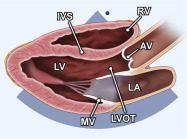

| 2.1. Mặt cắt trục dài cạnh ức với depth sâu

Cửa sổ siêu âm cạnh ức

Mặt cắt trục dài cạnh ức Đầu dò đặt tại bờ trái xương ức với marker hướng lên vai phải của bệnh nhân. |

Khoang màng ngoài tim Khoang màng phổi | |||||

| 2.2. Mặt cắt trục dài cạnh ức khu trú vào thất trái

Cửa sổ siêu âm cạnh ức

Mặt cắt trục dài cạnh ức Đầu dò đặt tại bờ trái xương ức với marker hướng lên vai phải của bệnh nhân. Chùm siêu âm đặt vuông góc với thất trái. |

Nhĩ trái (LA)

Van hai lá (MV) Thất trái (LV) Đường ra thất trái (LVOT) Van động mạch chủ (AV) Vách liên thất (IVS) Thất phải (RV) |